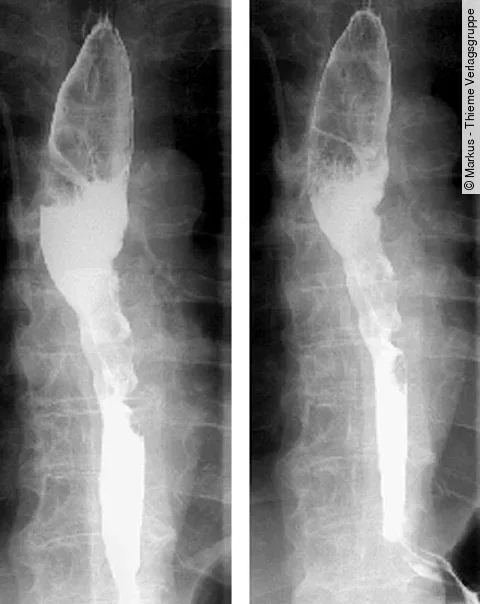

Quiz der Woche: Auflösung: 74-Jähriger mit Schluckstörungen

Der Ösophagusbreischluck zeigt eine Raumforderung im Ösophagus. Doch nur eine der drei Antwortmöglichkeiten ist die korrekte Diagnose. Lagen Sie richtig?